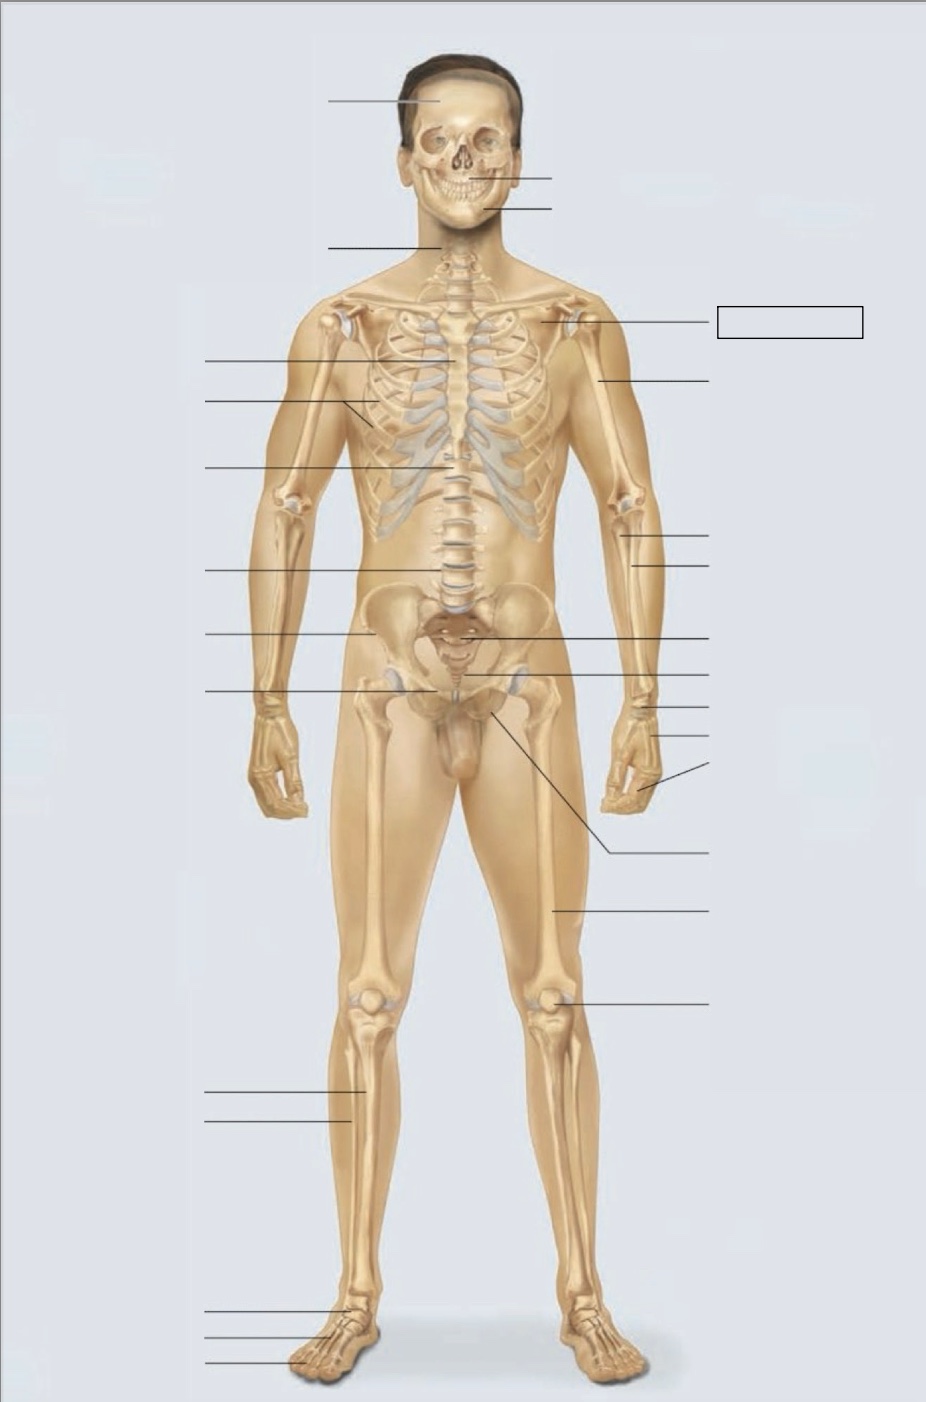

maxilla

mandible

scapula

humerus

ulna

radius

sacrum

coccyx

carpals

metacarpals

phalanges

ischium

femur

patella

phalanges

metatarsals

tarsals

fibula

tibia

pubis

ilium

lumbar vertebrae (L4)

thoracic vertebrae (T11)

ribs

sternum

cervical vertebrae

skull